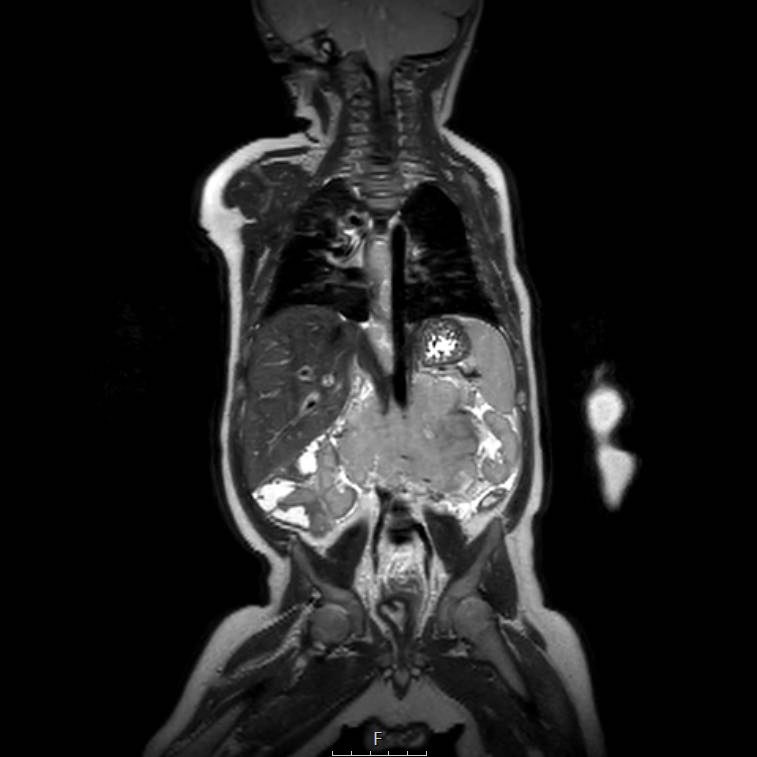

Ví dụ 1

Một bé gái ba tuổi có khối u thận trái và huyết khối khối u lớn trong tĩnh mạch thận và tĩnh mạch chủ dưới. Có di căn gan (phát hiện không thường gặp) và di căn phổi.

Lưu ý huyết khối u trong tĩnh mạch thận trái kéo dài vào tĩnh mạch chủ dưới.

Chuỗi ảnh MRI axial trọng số T2 cho thấy huyết khối u lan rộng đến mức tĩnh mạch gan. Lưu ý phần còn lại giãn rộng của hệ thống thu thập nước tiểu